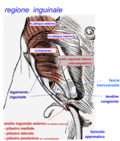

muscles of the human torso

Media in category "Muscles of the human torso"

The following 90 files are in this category, out of 90 total.